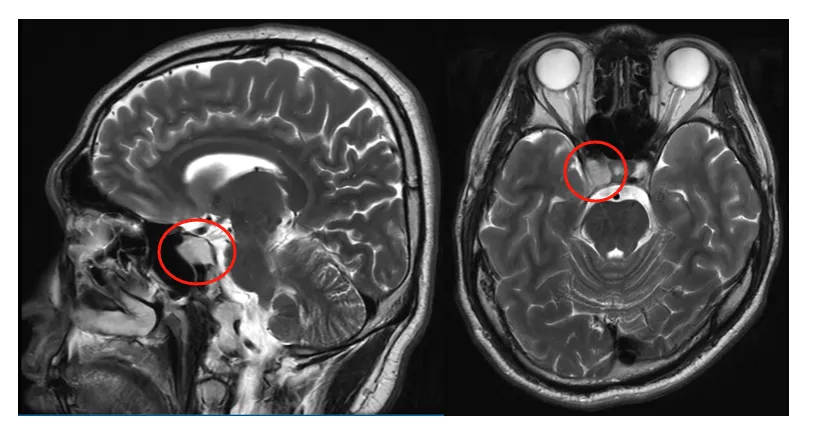

29岁的张先生可能从未想过,一次普通的鼻炎检查,竟会意外发现颅底深处的隐患——“鞍旁表皮样囊肿”。尽管最初的头痛、头晕已逐渐消失,但身体仍不时发出警报:莫名的平衡感下降、轻微的眩晕,提示着问题并未真正消失。

这个位置刁钻的囊肿,已经压迫到海绵窦内密布的多条颅神经(第三、四、五、六对)。是做手术主动干预,还是继续观察保守治疗?在辗转求医的过程中,他了解到INC的福教授,一位专擅颅底手术的大咖。

术前影像